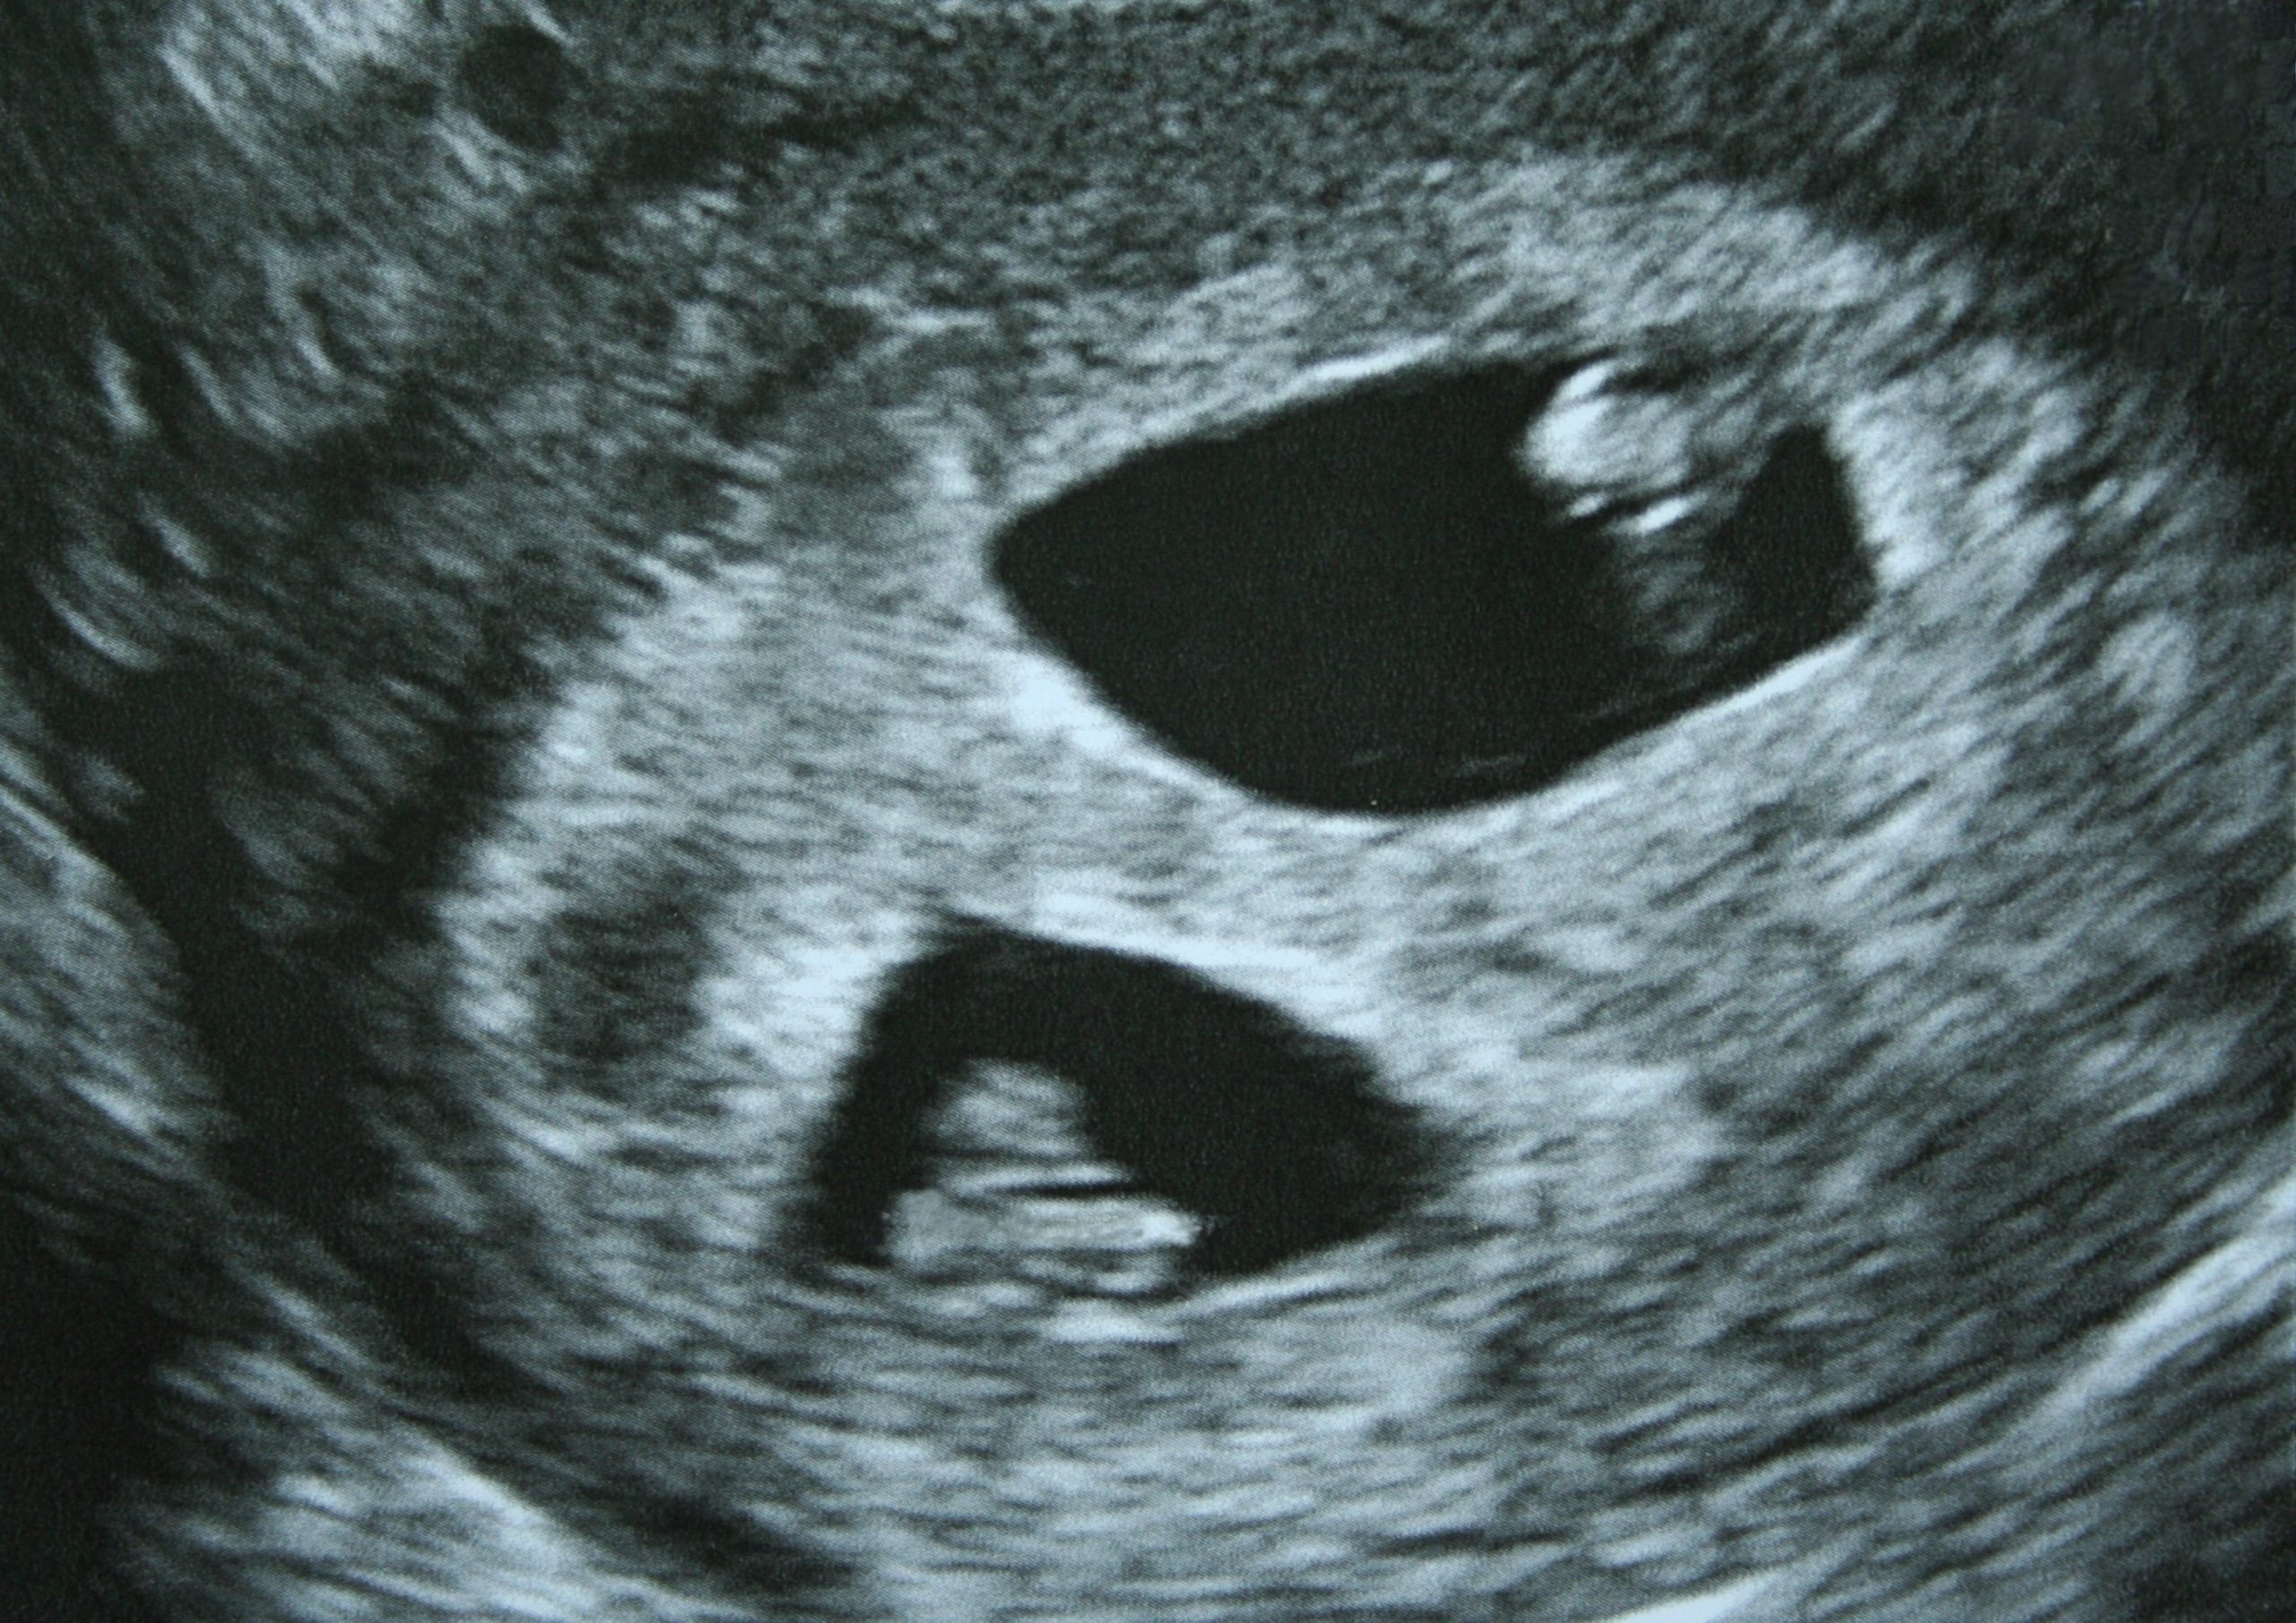

Ultrasound Images Of Vanishing Twin . Advances in ultrasonography enabled detection and monitoring of a vanishing twin in evolution. Live, single fetus of about 15 weeks by usg. Vanishing twin in a twin pregnancy at 31 weeks gestation. Vanishing twin syndrome, as the name depicts, is a condition in which one of a. (a) a dichorionic diamniotic twin. Ultrasound images in the first trimester of: Histopathologic and genetic investigation of remnant. This is a follow up ultrasound image. May range from crescentic gestational sac to normally formed but dead fetus later in pregnancy.

Live, single fetus of about 15 weeks by usg. Vanishing twin in a twin pregnancy at 31 weeks gestation. This is a follow up ultrasound image. Ultrasound images in the first trimester of: Histopathologic and genetic investigation of remnant. May range from crescentic gestational sac to normally formed but dead fetus later in pregnancy. Vanishing twin syndrome, as the name depicts, is a condition in which one of a. (a) a dichorionic diamniotic twin. Advances in ultrasonography enabled detection and monitoring of a vanishing twin in evolution.

Ultrasound Images Of Vanishing Twin Vanishing twin syndrome, as the name depicts, is a condition in which one of a. (a) a dichorionic diamniotic twin. Ultrasound images in the first trimester of: Advances in ultrasonography enabled detection and monitoring of a vanishing twin in evolution. Vanishing twin syndrome, as the name depicts, is a condition in which one of a. May range from crescentic gestational sac to normally formed but dead fetus later in pregnancy. Histopathologic and genetic investigation of remnant. Vanishing twin in a twin pregnancy at 31 weeks gestation. This is a follow up ultrasound image. Live, single fetus of about 15 weeks by usg.